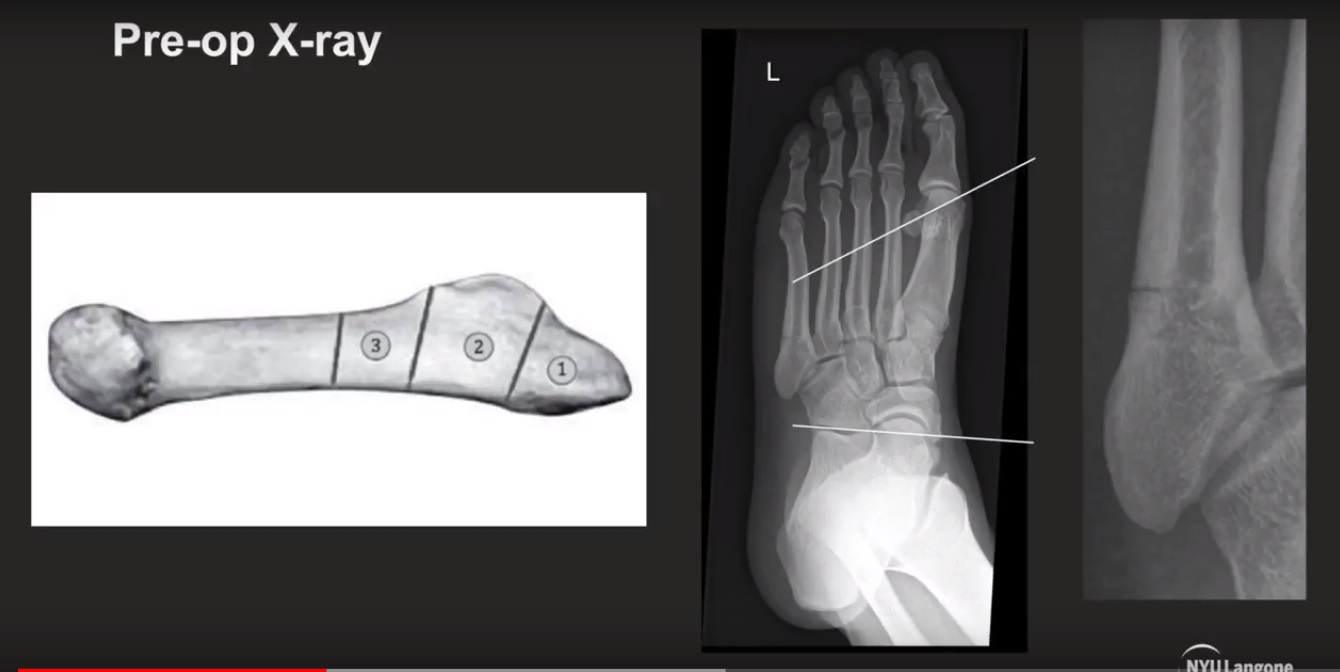

2. Fifth Metatarsal Fractures

Jones Fracture (Zone 2)

Occurs in a vascular watershed area.

Located in the proximal fifth metatarsal.

Often enters the fourth and fifth intermetatarsal articulation.

Zone 1 Fracture (Pseudo-Jones)

Enters the tarsometatarsal joint (metatarsocuboid joint).

Zone 3 Fracture

Proximal diaphyseal fracture distal to the fourth and fifth articulation.